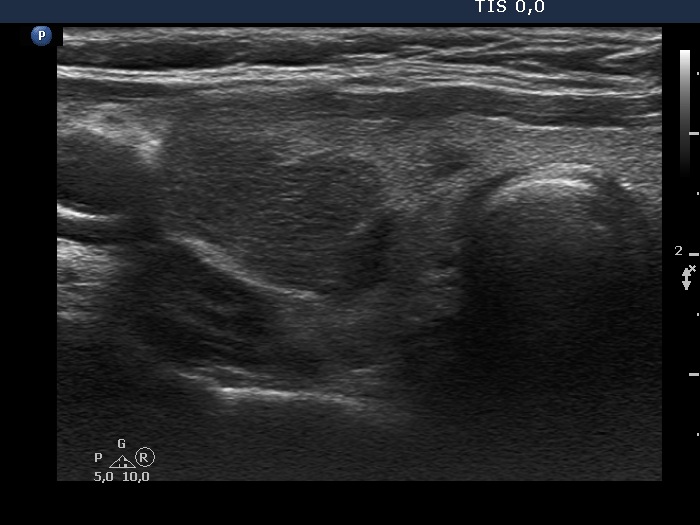

First examination (first, third and fifth rows of images):

Ultrasonography. The thyroid was echonormal and contained multiple inhomogeneous, partly blurred hypoechogenic and moderately hypoechogenic discrete lesions. Multiple lymph nodes were found on both sides of the neck.